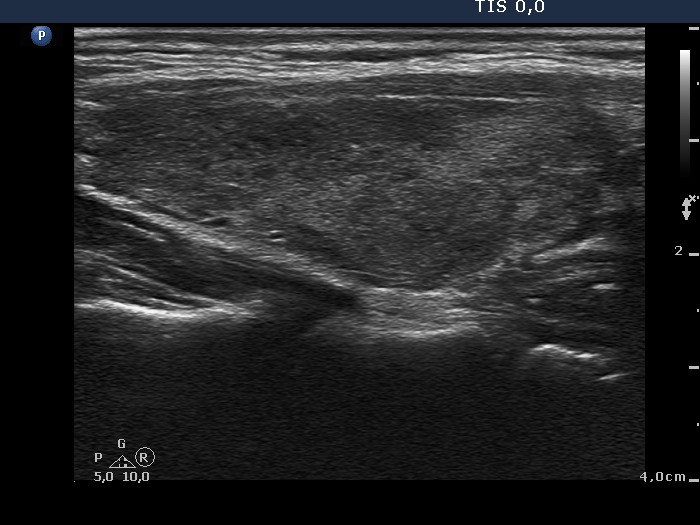

Present examination (ultrasonographic picture 9)

Left lobe, longitudinal scan.